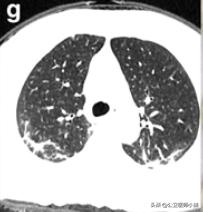

肺部好转

如果患者得到有效的治疗,或者患者症状较轻免疫力成功抵抗了病毒,炎症将进一步吸收程度开始降低。

开始恢复的肺